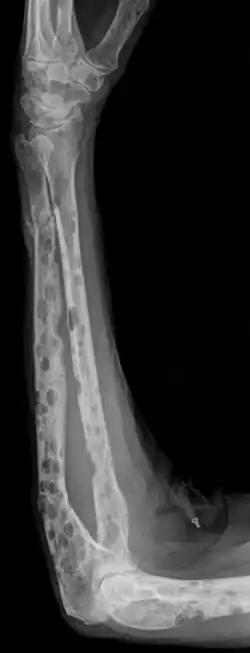

- Starker Knochenabbau/-schäden durch Osteolyse (die Schäden wirken im Gegensatz zu Knochenmetastasen wie ausgestanzt – typisch: Schrotschussschädel)

- Durch die Osteolyse bedingte Knochenschmerzen und Knochenbrüche

- Knochenläsionen mit mindestens einer osteolytischen Läsion, nachweisbar durch Röntgen, CT oder PET-CT.